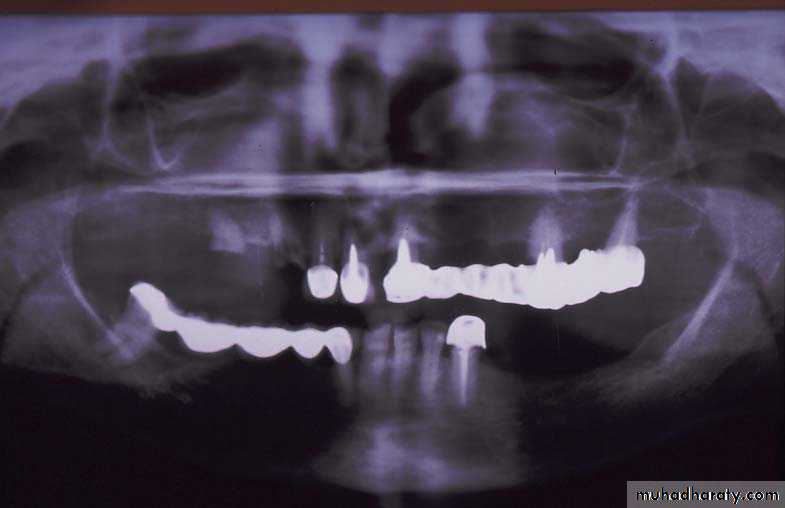

Evaluation of radiographic survey

All prospective abutment teeth must be critically evaluated4/2/2018

Root size, length and form

Teeth with large or long roots - Greater periodontal supportTapered or conical roots- un favorable

Multi rooted teeth with divergent roots are stronger abutment teeth than single rooted, multi rooted teeth with fused roots.4/2/2018

Signs of positive bone factor

A supportive trabecular patternHeavy cortical layer

Dense lamina dura

Normal bone height

Normal periodontal ligament space.

If retrograde bone changes occur, the patient has a negative bone factor ; prognosis is poor.